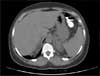

A CT scan of the abdomen with contrast performed as part of an evaluation of the chronic diarrhea revealed a Bochdalek hernia.

This congenital defect, first described by Bochdalek in 1848, is an improper fusion of the posterolateral foramina of the diaphragm that results in herniation of the abdominal organs into the chest cavity. Because the left abdominal canal closes later than the right during embryogenesis, 85% of cases involve the left side of the diaphragm.1

Bochdalek hernia occurs in about 1 of 2200 to 2500 live births and affects males twice as often as females. The defect may cause respiratory or GI symptoms at birth; however, it may remain asymptomatic. In adults, Bochdalek hernia is primarily an incidental finding on a CT scan of the abdomen, as it was in this patient. Its incidence in asymptomatic adults varies between 0.17%2 and 6%.3